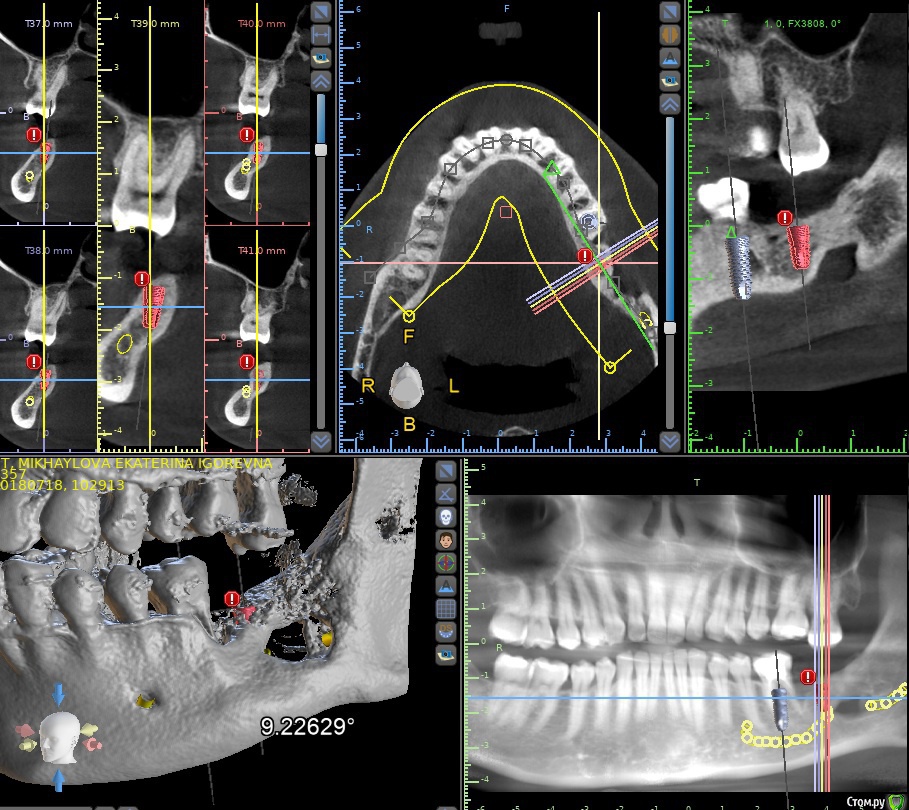

Jurai Опубликовано 28 июня, 2019 Поделиться Опубликовано 28 июня, 2019 (изменено) Пациент после удаления цементомы (2014г). Одномоментно были удалены 37, 38, костная пластика не проводилась. Парестезия есть - нижняя губа, подбородочная область. У меня три варианта - 1)удаление 36, имплантация 36, имплантация 37 вот в тот участочек + НКР. Интрузия 27. 2) Радикальное вмешательство для ликвидации сквозного дефекта кости, потом имплантация. Неизвестно что там получится. Интрузия 27. 3) удаление 27, удаление и имплантация 36 и хватит. Что предпочтительнее? Дайкомы КЛКТ https://yadi.sk/d/2lUunZHG0JfW2w Изменено 28 июня, 2019 пользователем Jurai Ссылка на комментарий

Jurai Опубликовано 28 июня, 2019 Автор Поделиться Опубликовано 28 июня, 2019 Дмитрий, почему? Имеющийся объем кости вполне позволяет позиционировать имплантат 37 в адекватной позиции для протезирования. Целесообразна по причине прогнозируемой потери 27 з. Пациенту не много лет. Ссылка на комментарий

Дмитрий Л. Опубликовано 1 июля, 2019 Поделиться Опубликовано 1 июля, 2019 Дмитрий, почему? Имеющийся объем кости вполне позволяет позиционировать имплантат 37 в адекватной позиции для протезирования. Целесообразна по причине прогнозируемой потери 27 з. Пациенту не много лет. 27 прогнозируемо можно спасти, а вот 36 очень неуверенно стоит на одной ножке. Меня смущают:1. Пародонтальный карман дистальнее 36.2. Возникающее в связи с этим риски перимукозита и т.д.3. Локализация имплантата в позиции 37 - костная образовавшаяся арка. Если будет отторжение (в т.ч. и в долгосрочной перспективе), то это принесёт немало хлопот, так как н.ч. будет держаться на оставшихся 2х см снизу, такой костный дефект трудно и дорого заместить.4. Всё это делается ради возмещения 10% жевательной эффективности и ни на что вцелом не повлияет. 3) удаление 27, удаление и имплантация 36 и хватит. Это будет удаление без показаний, так нельзя) Я понимаю, что технически можно сделать всё что угодно, но стоит ли браться за этот гемор ради имплантации 1 единицы?По крайней мере теперь у вас есть контр-аргументы Кстати интрузировать можно и имплантом (37), если решитесь. Ссылка на комментарий

Jurai Опубликовано 2 июля, 2019 Автор Поделиться Опубликовано 2 июля, 2019 Я понимаю, что технически можно сделать всё что угодно, но стоит ли браться за этот гемор ради имплантации 1 единицы? А вы мой вопрос и варианты лечения внимательно прочитали? Особенно первый? Для 27 показания к удалению - травмирующий фактор для слизистой, пациент не может нормально жевать, прикусывает щеку, на ней уже рубец. Имплантат в позиции 37 медиальнее арки. Ссылка на комментарий